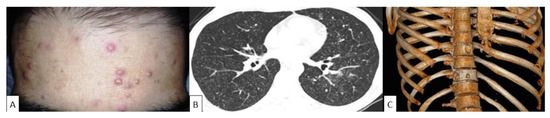

- De Freitas, R.S.; Dantas, K.C.; Garcia, R.S.P.; Magri, M.M.C.; de Andrade, H.F. Paracoccidioides brasiliensis causing a rib lesion in an adult AIDS patient. Hum. Pathol. 2010, 41, 1350–1354. [Google Scholar] [CrossRef] [PubMed]

- Porro, A.M.; Rotta, O. Cutaneous and pulmonary paracoccidioidomycosis in a patient with a malignant visceral tumor. Anais Bras. Dermatol. 2011, 86, 1220–1221. [Google Scholar] [CrossRef]

- Covre, L.C.P.; Hombre, P.M.; Falqueto, A.; Peçanha, P.M.; Valim, V. Pulmonary paracoccidioidomycosis: A case report of reactivation in a patient receiving biological therapy. Rev. Soc. Bras. Med. Trop. 2018, 51, 249–252. [Google Scholar] [CrossRef]